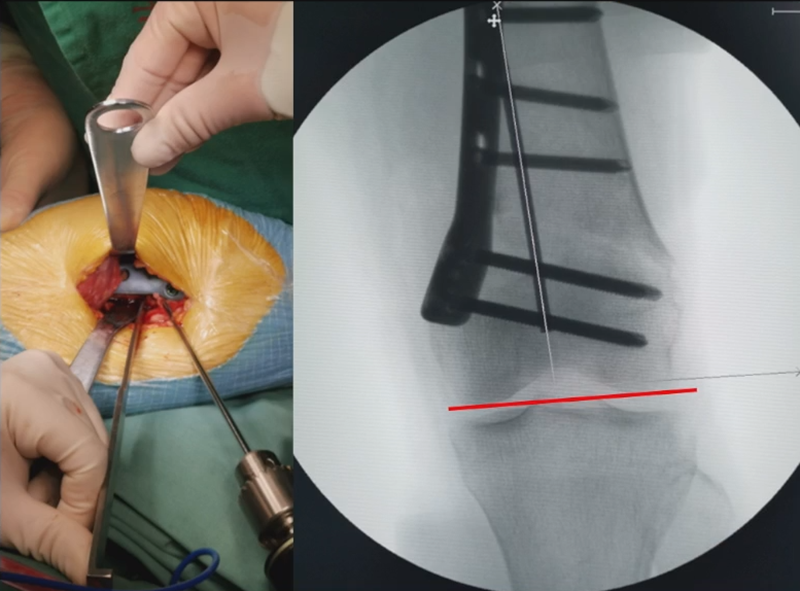

3、选择合页位置和截骨线

合页点的选择与HTO一样,通常需要尽可能接近畸形部位,既要有很好的骨质结构,还要有坚韧的软组织覆盖,以保证稳定性和术后有良好的血运。合页宽度不宜太长,通常保留在5mm。

合页点定位有两种方法,一种为定位在股骨外后髁上缘2mm位置,通常将此区域叫做“鹰嘴区”,以此为解剖标记法来定位合页点。

另一种通过导针从截骨入点向股骨外后髁后缘打出一条切线,此切线与外侧骨皮质的交点,也可作为合页点,这种方法称为导针法。这两种方法在手术之中是可以互为验证的。

合页点处于松质骨区,易形变区,如选择周边区域较脆易折断。另外合页点后方有小腿三头肌的附着点,有很好的的软组织和血运,综合来说作为合页非常合理。

4、截骨

合页点和截骨线已确定好,按照术前计划打入导针,测量截骨深度。